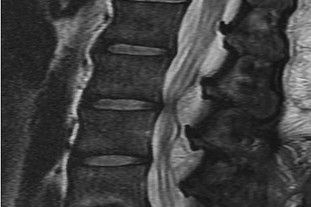

Question 8:

A 65-year-old male presents with classic symptoms of neurogenic claudication. He reports bilateral leg pain and fatigue that worsens with walking but is reliably relieved by leaning forward onto a shopping cart. In the pathogenesis of degenerative lumbar spinal stenosis, which structure is primarily responsible for dynamic central canal compression during spinal extension?

Correct Answer: Ligamentum flavum

Explanation:

In degenerative lumbar spinal stenosis, extension of the spine decreases the sagittal diameter of the canal because the ligamentum flavum buckles inward (shingling), dynamically compressing the thecal sac. Flexion of the spine pulls the ligamentum flavum taut, increasing the available canal space and alleviating neurogenic claudication symptoms. Hypertrophic ligamentum flavum is a major structural contributor to central stenosis.